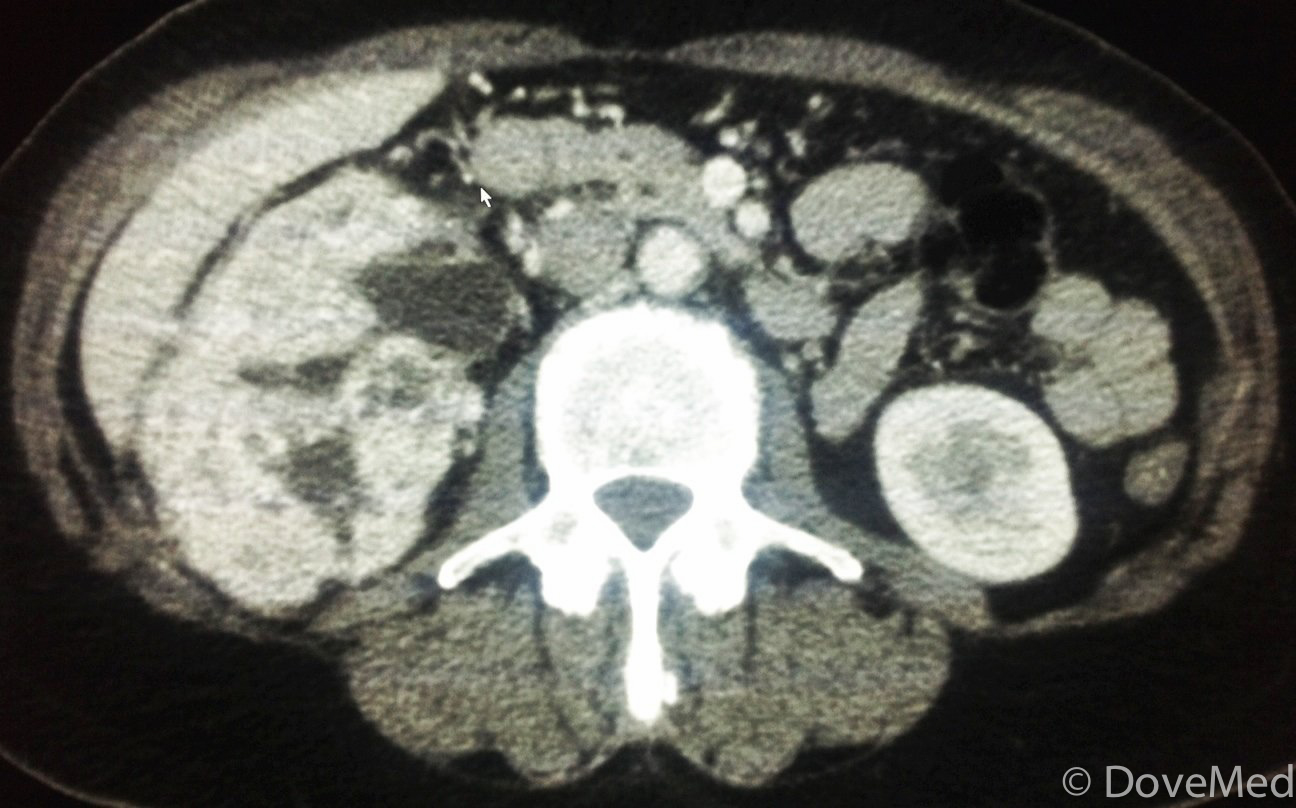

From www.dovemed.com

Radiofrequency Ablation of Kidney Tumor Kidney Ablation Side Effects if you develop side effects, they can develop any time during, immediately after or a few days or weeks after ablation therapy. possible side effects include bleeding and damage to the kidneys or other nearby organs. ablation for kidney cancer uses extreme heat (radiofrequency ablation) or cold (cryoablation) to destroy kidney. the preferred treatment for localized. Kidney Ablation Side Effects.